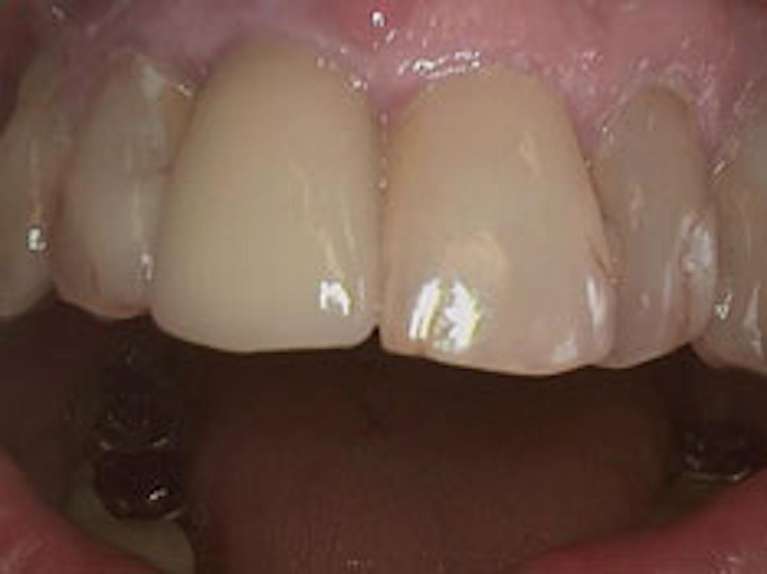

This patient presented with a missing front tooth requiring a permanent, durable solution. We placed a custom dental implant topped with a high-quality porcelain crown. Notice the precise color matching and the way the crown mimics the light-reflecting properties of natural enamel. The result is a secure, functional restoration that restores the "anchor" of the patient's smile.